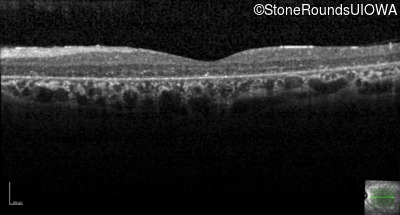

Optical Coherence Tomography - Right - 10/600 sc

Exemplar / OCT Stack

OCT Stack